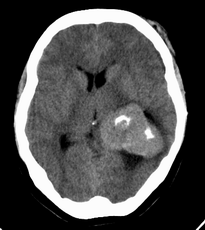

患者,女性,33岁,外伤检查发现,既往没有明显类似病史。

ct平扫见左侧脑室后角不规则形,边界不清的等密度肿块,肿瘤内有钙化,瘤周可见残存的脑室(低密度脑脊液影),考虑脉络脉丛乳头状瘤或室管膜瘤.

左侧侧脑室三角区占位性病变,其特点是平扫边界清、密度高、其内可见大块结节样的钙化,首先考虑起源于侧脑室三角区残余蛛网膜上皮的脑膜瘤可能性最大,无论是形态、密度、好发部位均符合脑膜瘤特点,建议增强进一步检查。

左侧脑室内软组织肿物,内部见多发不规则钙化,边界清楚锐利,有分叶。相应左侧脑室扩张。常见的不外乎3种病:室管膜瘤,脑膜瘤,脉络脉丛乳头状瘤。脑膜瘤分叶较少见,脉络脉丛乳头状瘤钙化较少见,因此,室管膜瘤可能性最大。

左侧脑室内见不规则略高密度团块影,边缘分叶,内见多发不规则钙化,病灶与侧脑室壁关系较为密切,左侧脑室扩大。考虑室管膜瘤可能性较大,其次为脑膜瘤,脉络丛乳头状瘤的可能性最小。

患者,女性,33岁,外伤检查发现,既往没有明显类似病史;

1、病灶除钙化外其它部分质均匀,无明显密度差别;

2、病灶界清,呈现膨胀性生长,对周围组织无明显浸润表现;

3、钙化部分范围较大,呈现大片状钙化;

4、病人为成年女性,无明显不适;

考虑:脑膜瘤;

鉴别诊断:室管膜瘤;脉络膜乳头状瘤;

平扫见左侧脑室三角区不规则形肿块,肿瘤内有钙化,瘤周可见残存的脑室(低密度脑脊液影),考虑脉络脉丛乳头状瘤或室管膜瘤.